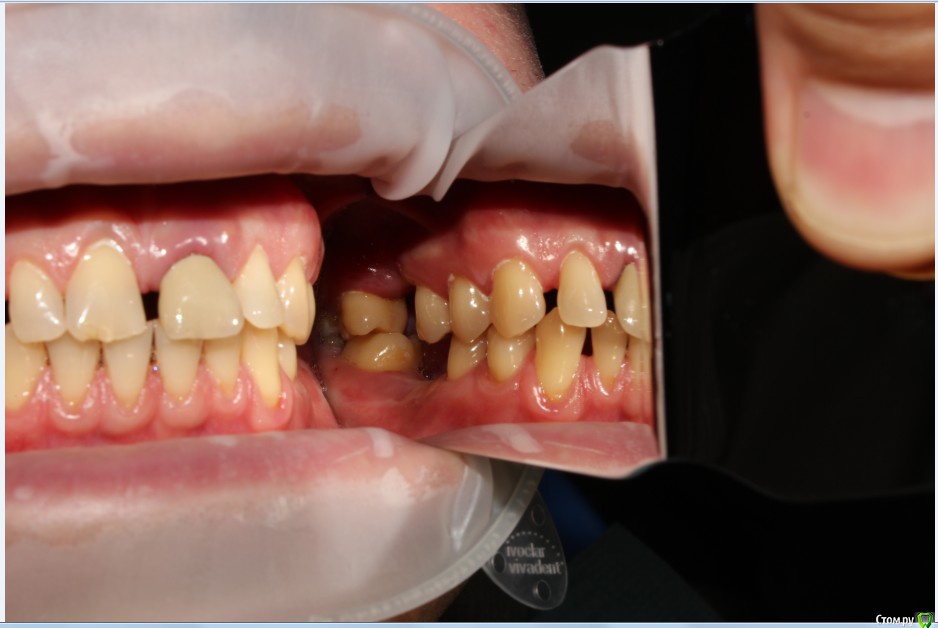

Рустам Опубликовано 20 июля, 2015 Поделиться Опубликовано 20 июля, 2015 Здравствуйте коллеги! Подскажите по клиническому случаю пожалуйста. Обратился пациент в клинику с подвижной коронкой на зубе 2.1, на рентгене диагностирован перелом корня, планируем удаление с одномоментной имплантацией и желательно с немедленной нагрузкой. Система имплантатов "Osstem", на этой системе я ранее не протезировал (работал с "Mis" и "Super Line") и вообще ранее немедленно не нагружал имплантаты. Хирург назначил удаление и иплантацию на 23.07, я смогу принять пациента только 24.07 утром, необходимо заказать временный абатмент, подскажите какой именно из каталога нужно заказать?Имплантолог заказал два имплантата Osstem TSIII SA диаметром 4,0 и 4,5.Я планирую делать временную прямым способом по ключу снятому со старой коронки во рту. Может лучше через оттиск заказать лабораторную временную?P.S. пациента эстетически все устраивало, ортодонтию не хочет. Ссылка на комментарий

Dr.Zoom Опубликовано 22 июля, 2015 Поделиться Опубликовано 22 июля, 2015 Давидян говорит, что перелом корня, впринципе, это противопоказание))) Ссылка на комментарий

Dr.Zoom Опубликовано 20 августа, 2015 Поделиться Опубликовано 20 августа, 2015 А можно по подробнее, или ссылку почитать, спасибо.если перелом корня длительное время не был диагносцирован- то существует большой риск инфецирования Ссылка на комментарий